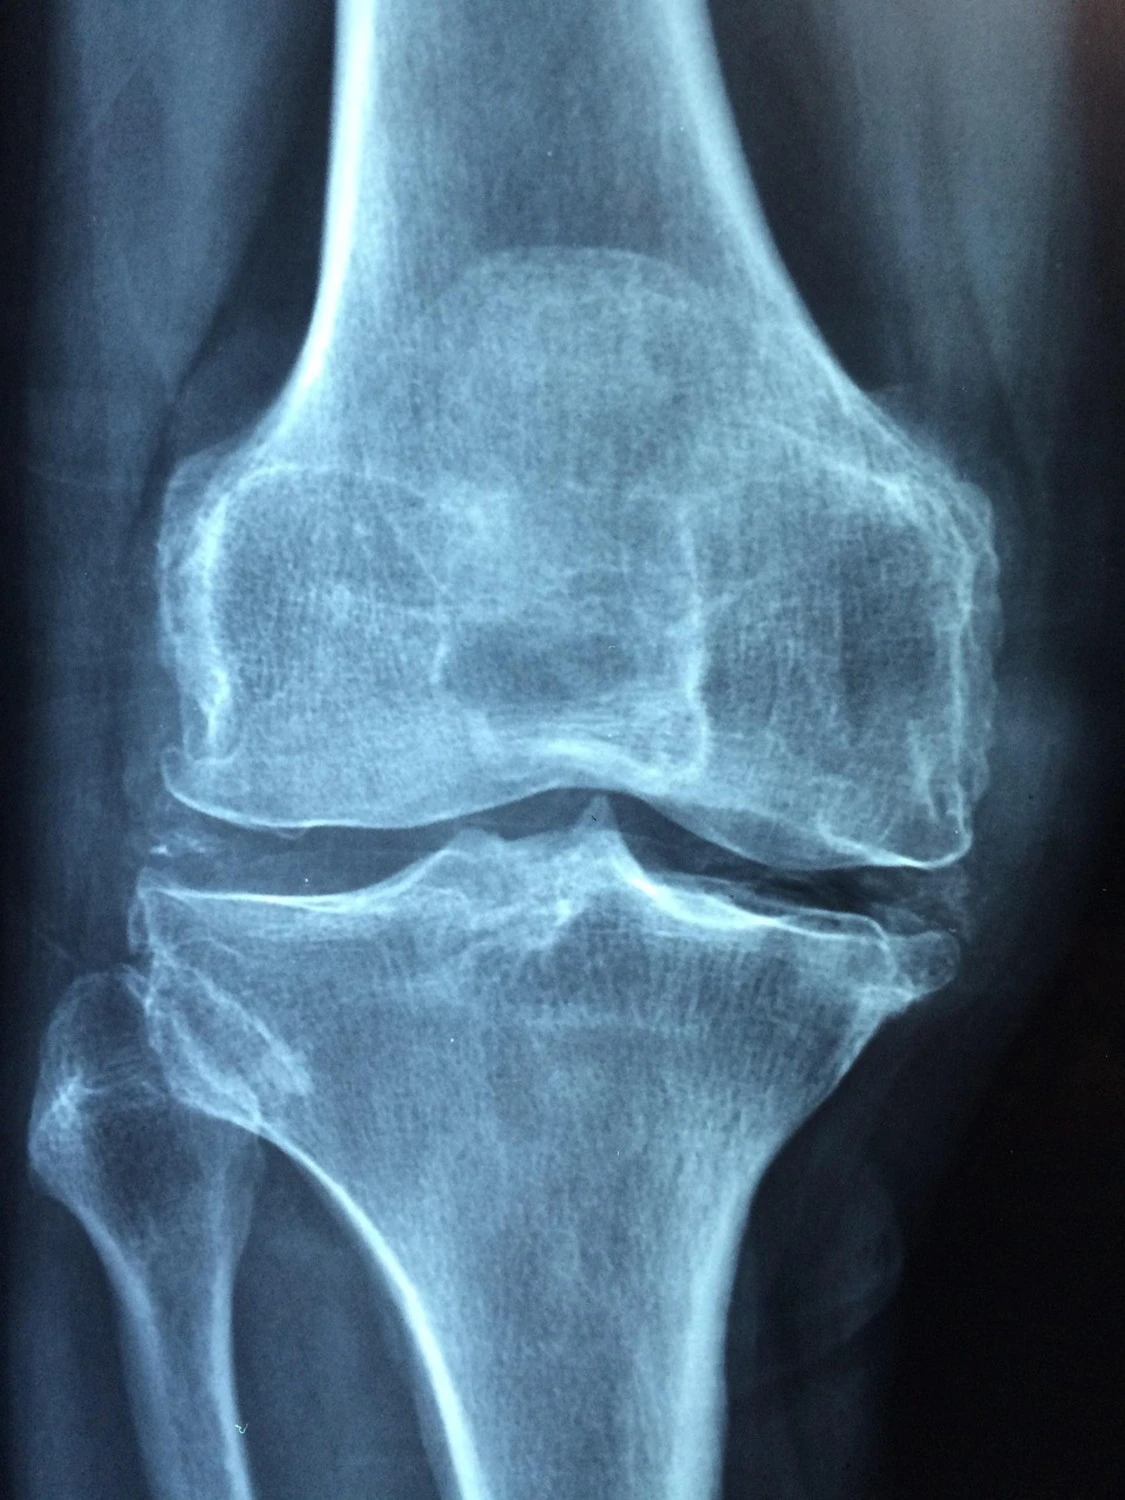

Il nome “osteoporosi” significa “osso poroso” e indica la formazione di cavità che alterano l’osso indebolendolo. “La familiarità è uno dei principali fattori di rischio - spiega Epis - ma non è l’unico. Le probabilità aumentano per esempio in chi consuma pochi latticini, in chi soffre di malattie reumatiche o patologie da malassorbimento come la celiachia, in chi ha utilizzato a lungo cortisonici, e in chi presenta ipercalciuria. Più a rischio anche le pazienti operate di tumore al seno e in terapia con inibitori dell’aromatasi. Fumo, abuso di alcol e avanzare dell’età completano il quadro. Nelle donne si ha un'accelerazione nella perdita di massa ossea soprattutto dopo la menopausa, quando la produzione di estrogeni cala bruscamente”.

La diagnosi parte dall’anamnesi, durante la quale lo specialista valuta familiarità, stile di vita, abitudini alimentari e comorbidità. Seguono esami del sangue e urine, utili a escludere cause secondarie. Ma la conferma arriva dagli esami specifici: la moc (mineralometria ossea computerizzata), che misura con precisione la densità minerale dell’osso. “le terapie disponibili oggi sono molto efficaci, permettono di rallentare la progressione della malattia e in alcuni casi anche di migliorare la massa ossea, ma la loro efficacia dipende dalla costanza. A un anno dall’inizio della cura solo la metà dei pazienti la prosegue. Per questo è necessario sensibilizzare sull'aderenza ai trattamenti e la diagnosi precoce: chi presenta uno o più fattori di rischio, ad esempio, dovrebbe valutare un controllo già intorno ai 50 anni”.